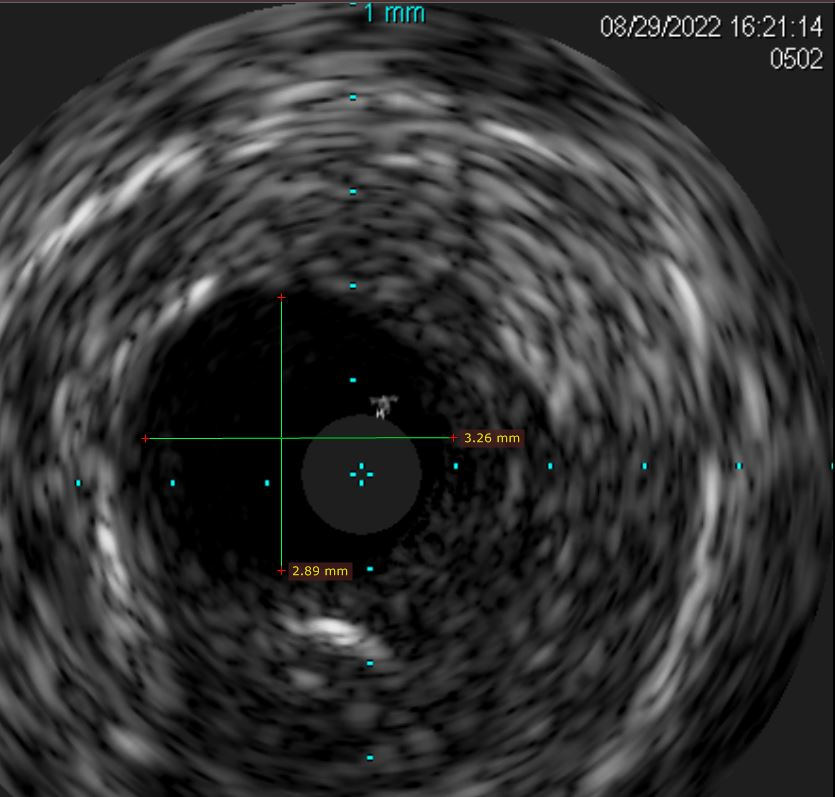

光学相关成像(OCT)显示右上肺动脉狭窄病变程度与宽度。

针对右上肺动脉狭窄病变采用小球囊逐级扩张,后用相应直径的割球囊再次扩张,达到预期后,再用药物球囊贴壁扩张,释放抗炎,防增生药物,以巩固治疗效果。全程应用肺动脉相控阵血管内超声(IVUS)显示右上肺动脉狭窄病变,同时准确测量需要球囊扩张的靶病变长度,避免血管损害,保证安全性。